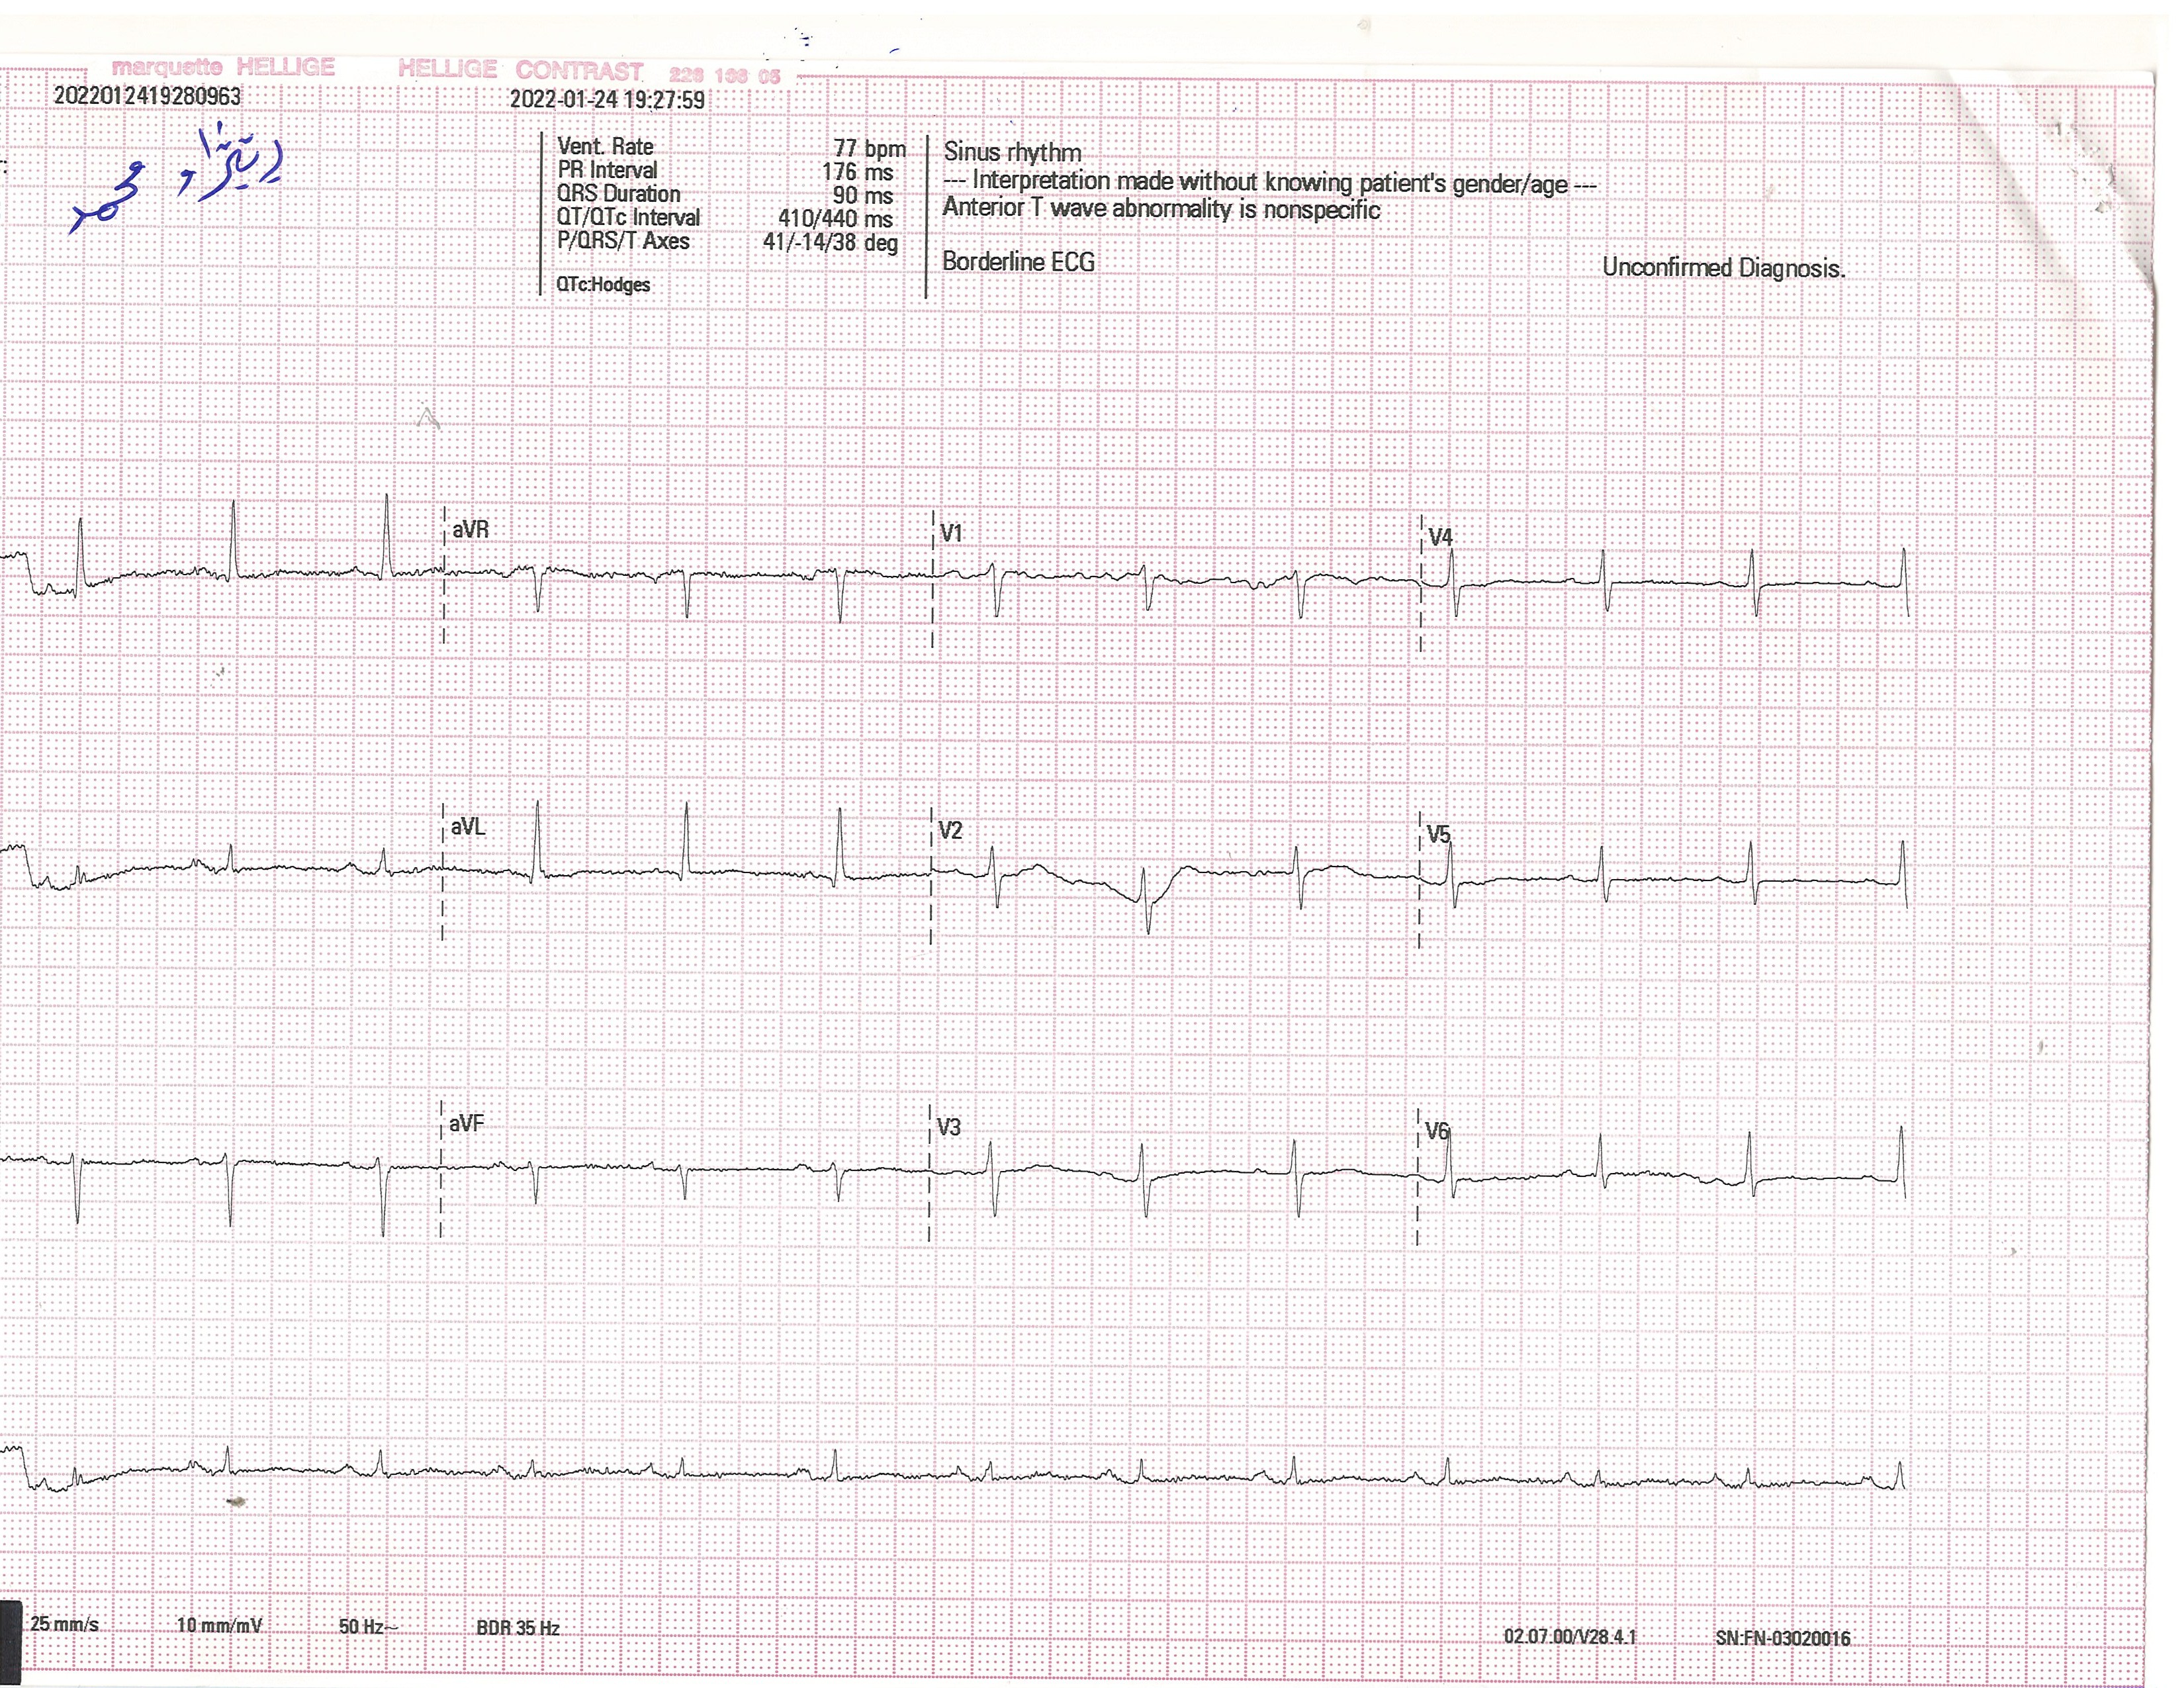

BP : 140/95     PR : 80     RR :     SPO2 : 94     CC : CHECK UP

ID : 4425      RIZHAW MHAMAD RASHED           1947             Female      W : kg     H : cm         Angio        HTN             HPI :